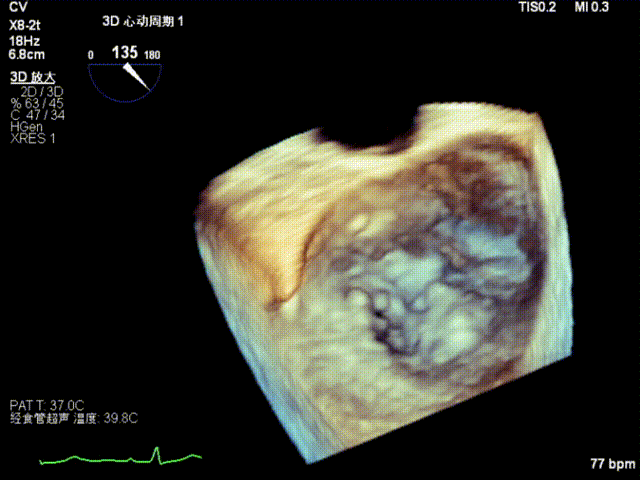

全麻后,二尖瓣夹合器系统在心前区的肋间切开3-4CM小切口,暴露心脏的心尖位置,送系统送入左心房,顺利到达病变二尖瓣区域。在经食道超声辅助下,术者通过反复评估二尖瓣反流位置、抓捕位置、反流程度,首先在2偏3区位置处于二尖瓣闭合线垂直进行巧妙夹合。在2区靠近3区位置处植入了1枚ValveClamp®MVC-IIf夹,最终评估评估反流降至轻度,平均跨瓣压差降至2mmHg,手术取得圆满成功。

术中超声(关键步骤)

最终在A3P2位置夹合,前叶夹合量10mm,后叶夹合量8mm,剩余瓣口面积3.45cm²,平均跨瓣压差2mmHg,反流基本消除。